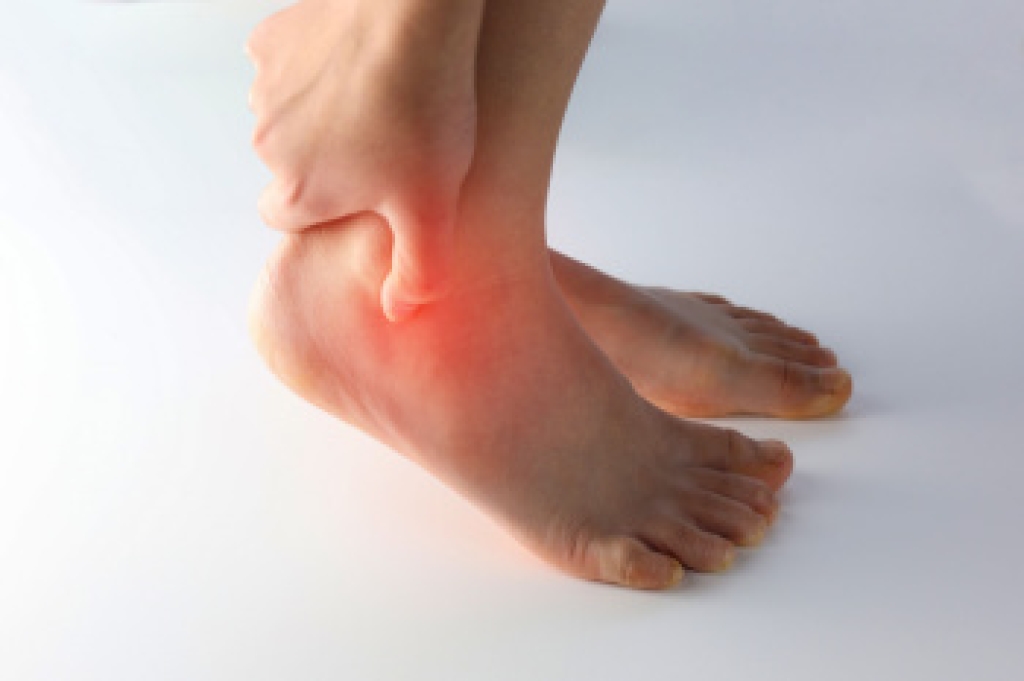

Gout in the ankle can cause sudden, intense pain, swelling, and redness that may be mistaken for a sprain. This type of inflammatory arthritis occurs when uric acid builds up in the bloodstream and forms crystals in the joint. The ankle becomes inflamed, often without prior injury, due to these deposits. Gout is more common in men over 40 and women after menopause. It can be triggered by a diet high in purines, certain medications, excessive alcohol use, or other medical conditions like kidney disease and diabetes. People with recurring gout attacks may develop long-term joint damage or reduced mobility, if the condition is not addressed. A chiropodist can help identify whether gout is affecting your ankle through clinical evaluation and may recommend ongoing treatment to reduce pain and manage uric acid levels. Addressing underlying health issues and modifying diet may reduce flare frequency. If you have ankle pain from gout, it is suggested that you schedule an appointment with a chiropodist for expert advice.

Gout is characterized by sudden, severe attacks of pain, redness, and tenderness in the joints. This type of arthritis is caused by a buildup of uric acid in the bloodstream. When uric acid crystallizes in a joint, often the joint of the big toe, it can bring about a gout attack.

Symptoms of gout include:

- Sudden and severe pain

- Swelling

- Redness

- Warmth

- Joint stiffness

- Joint deformity